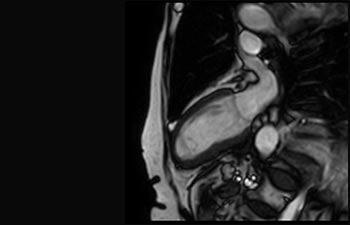

Find the right clinical applications for your needs